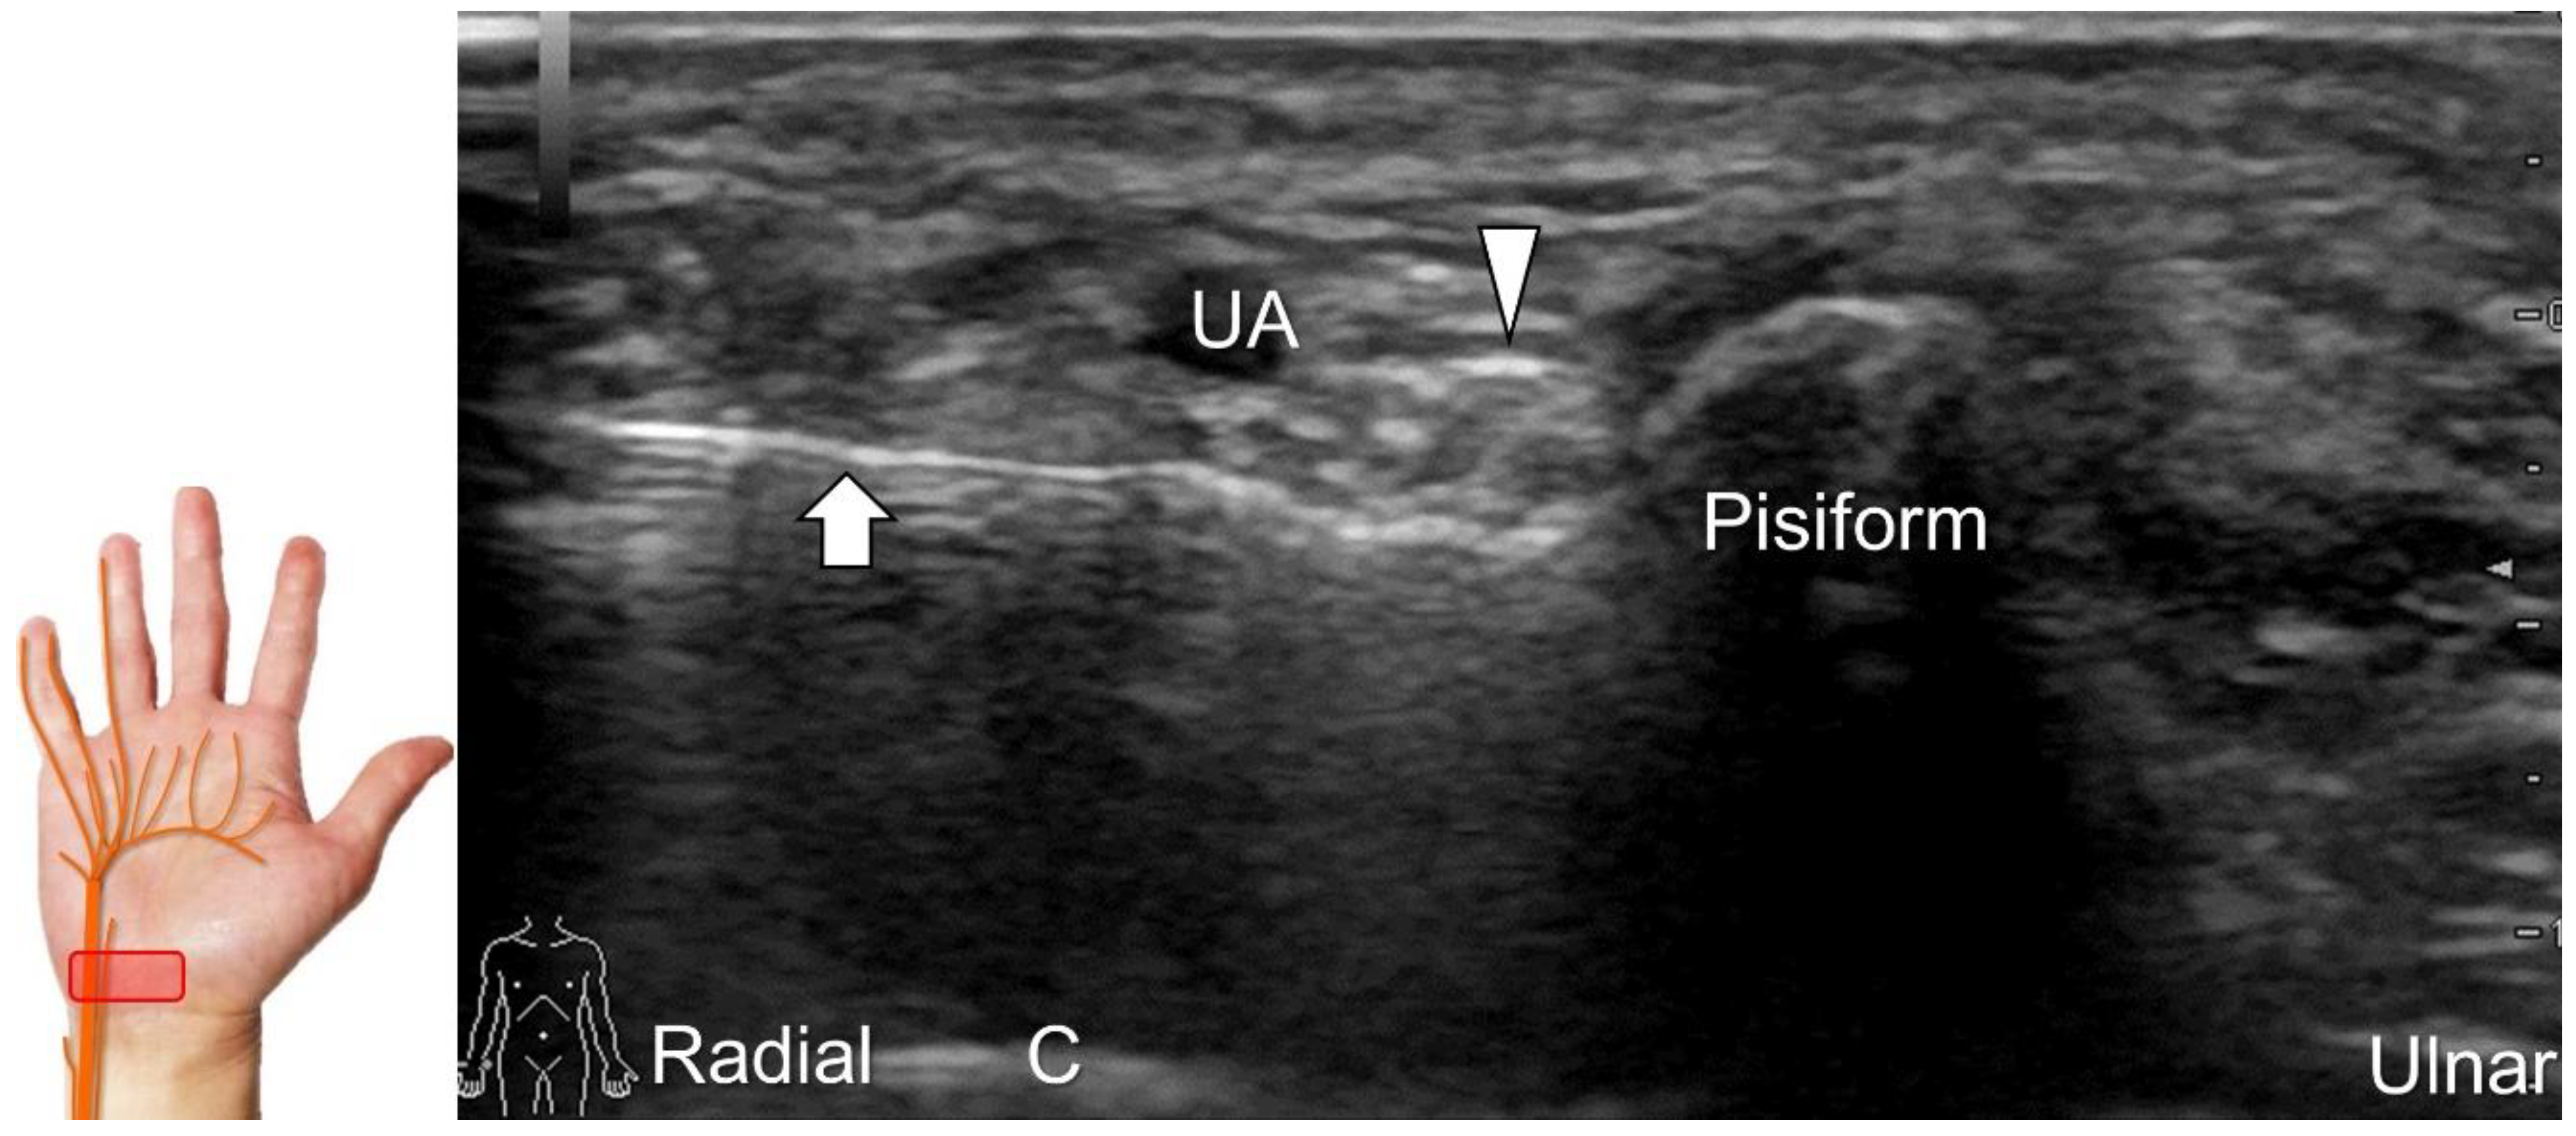

Scanning Technique

To locate the Guyon’s canal, the transducer is placed along the axial plane on the volar wrist with the forearm supinated. This will reveal the ulnar nerve and artery within the canal (Figure 13A). To investigate the nerve’s long axis, the transducer is rotated 90 degrees. By moving the transducer toward the finger, the superficial and deep branches can be seen. Between the pisiform and hamate, the superficial and deep branches (along with their accompanying vessels) can be visualized as separated by the fibrous arch of hypothenar muscles, respectively (Figure 13B) [39].

The superficial branch divides into two palmar digital nerves. They run superficially along the little finger and half of the ring finger. The deep branch, on the other hand, can be observed between the flexor digiti minimi brevis and opponens digiti minimi muscles before it penetrates the deep aspect of the palm (Figure 13C). By pivoting the transducer, the physician can display the long axis of the deep branch, extending all the way to the segment within the adductor pollicis muscle (Figure 13D).

Figure 13. Sonographic imaging (short-axis view) shows the ulnar nerve within the Guyon’s canal (A), separation of branches beside the pisohamate hiatus (B), deep branch of the ulnar nerve located between the hypothenar muscles distal to the hook of the hamate (C). Long-axis view (through pivoting the transducer) shows the segment of the deep branch within the adductor pollicis muscle (D). Arrowhead: ulnar nerve; white arrows: superficial branch of the ulnar nerve; black arrows: deep branch of the ulnar nerve; orange arrow: branch of the ulnar nerve to the abductor digiti minimi; *: pisohamate ligment MN: median nerve; UA: ulnar artery; P: pisiform; H: hook of hamate; A: artery; L: lumbrical muscle; FDM: flexor digiti minimi brevis muscle; Opp DM: opponens digiti minimi muscle; AbDM: abductor digiti minimi muscle; AdP: adductor pollicis muscle.